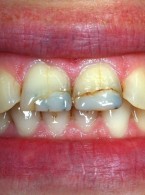

Pokrycie mnogich recesji dziąsłowych

metodą płata przesuniętego dokoronowo z wykorzystaniem przeszczepu podnabłonkowej tkanki łącznej i kolagenowego materiału ksenogennego po wcześniejszej rekonstrukcji połączenia szkliwno-cementowego - opis przypadku